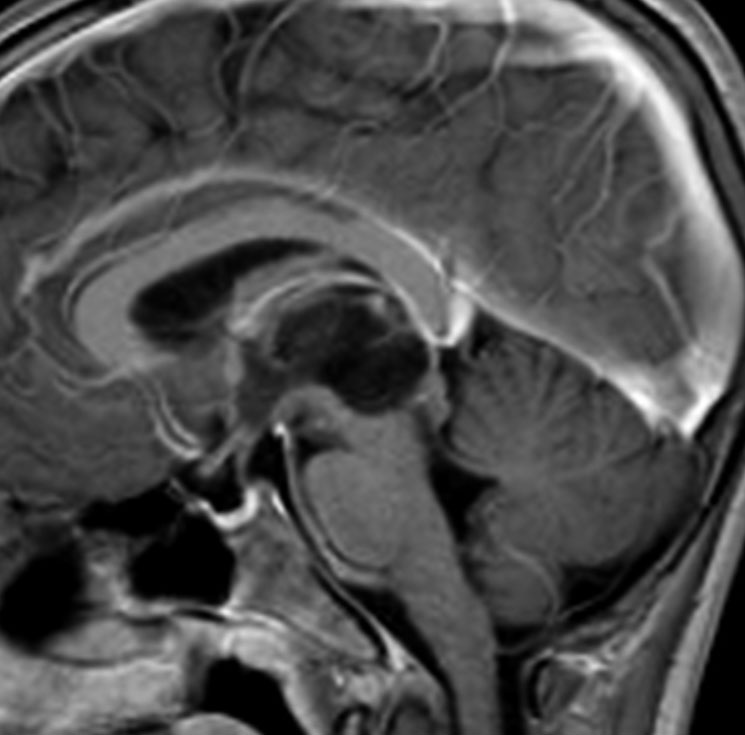

MRIです

左の拡散強調画像で高信号となり類表皮のう胞 epidermoid cyst あるいは類皮のう胞 dermoid cyst の診断です。しかし右のT2強調画像では左後方に違う信号の腫瘍塊があります。

ガドリニウム増強像です。類皮のう胞(成熟奇形腫 mature teratoma)との混合性胚細胞腫瘍を強く疑う所見です。